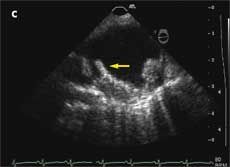

A previous transthoracic echocardiogram with a bubble study did not reveal any cardiac source of embolism. Axial MRI of the brain on admission showed an abnormal signal in the bilateral hemispheres representative of multiple subacute infarcts (Aand B); the right posterior frontal and right posterior parietal cortical and subcortical regions appeared to be most affected. A transesophageal echocardiogram revealed a severely thick atherosclerotic plaque with a large pedunculated mobile complex atheroma (C, arrow) in the upper descending aorta; the aortic arch showed severe atherosclerotic plaques with maximal thickness up to 10 mm (D).

Atherosclerotic plaques of 4 mm or greater in the aortic arch are significant predictors of recurrent brain infarctions. Transesophageal echocardiography should be considered for early detection in patients with an unidentified source of embolism.